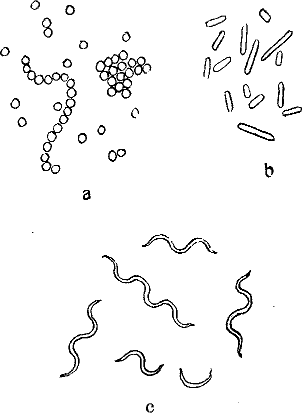

Ein halbes Jahrhundert später erst gelang es den geschickten Händen Antony van Leeuwenhoeks, kleine Linsen so sorgfältig und gleichmäßig zu schleifen, daß sie alle bis dahin angefertigten an Vergrößerungskraft übertrafen; er vervollkommnete hierdurch und durch kleine anderweitige Kunstgriffe seine optische Ausrüstung in bisher noch nicht dagewesenem Maße und untersuchte nun – von Haus aus ohne jede naturwissenschaftliche Ausbildung – mit ihrer Hilfe allerhand Flüssigkeiten: Regenwasser, Pflanzenaufgüsse, Darminhalt von Tieren und Menschen, den eigenen Speichel u. a. m. mikroskopisch.[3] Überall fand er – bald reichlicher, bald spärlicher – kleinste, vollkommen farblose »Tierchen«, die verschieden gestaltet, zum Teil lebhaft beweglich waren. Dank einer vorzüglichen Beobachtungsgabe und ebenso großer Zuverlässigkeit beschrieb Leeuwenhoek diese »Tierchen« so genau, daß wir sie heute mit Sicherheit als Bakterien wiedererkennen können. Auch gab er durchaus naturgetreue Abbildungen von ihnen, die die drei Hauptformen der Spaltpilze vollkommen richtig darstellen: alle die unzähligen Bakterien, die seitdem beobachtet worden sind, lassen sich ihrer Gestalt nach in kugelförmige (Mikrokokken), stäbchenförmige (Bazillen) und schraubenförmige (Spirillen) scheiden (s. Abb. 1). Freilich wechseln sie nach Dimensionen und kleinen Einzelheiten ihres Baues, wie wir sehen werden, in mannigfaltigster Weise, aber alle lassen sich auf einen der drei schon von Leeuwenhoek unterschiedenen Grundtypen zurückführen.

Bei einiger Übung werden wir aber bald erkennen, daß wir ein Kugelbakterium, ein Stäbchen- oder ein Schraubenbakterium vor uns haben. Mit wachsender Übung vermögen wir – unter Umständen auf den ersten Blick – besonders charakteristische Bakterienarten zu erkennen. Anderseits können wir bei sorgfältiger Beobachtung feine Unterschiede der Formen unter den Angehörigen der drei Grundtypen bald auffinden: so weichen z. B. manche Mikrokokken ein klein wenig von der Kugelgestalt ab, sie sind ein wenig abgeplattet; eine andere Art ist ein klein wenig längsoval, usf. Zur[13] Unterscheidung der Kugelbakterienarten, die im allgemeinen der Eigenbewegung ermangeln, kann uns auch die Art ihrer Lagebeziehungen im hängenden Tropfen wichtige Dienste leisten. Manche Arten bilden in einer Kultur regelmäßig perlschnurartige, kürzere oder längere, 3 bis 5, ja bis 30 und mehr einzelne Glieder aufweisende Ketten (Kettenkokken oder Streptokokken, vgl. Abb. 28, 29). Andere dagegen lagern sich zu weintraubenförmigen Häufchen zusammen und werden danach als Staphylokokken (ἡ σταφυλή die Weintraube) bezeichnet (vgl. Abb. 26). Zwischen den verschiedenen Arten der Stäbchen- und Schraubenbakterien bestehen ferner Unterschiede nach der Länge und Dicke und nach dem Verhältnis des Längen- zum Dickendurchmesser: so begegnen wir langen und schlanken, langen und plumpen, kurzen und schlanken, kurzen und plumpen Stäbchen- und Schraubenformen. Wenn wir sie genau betrachten, so können wir oft noch weitere feine Unterschiede zwischen den verschiedenen Arten erkennen: die einen besitzen abgerundete Enden, die anderen kantige, manche zeigen die Neigung, dadurch, daß mehrere Individuen aneinander haften, Fäden zu bilden, und so gibt es noch eine ganze Reihe feiner Gestaltmerkmale, die der sorgfältige Beobachter zu berücksichtigen hat.

Unter den Lebensvorgängen, die der unmittelbaren Beobachtung zugänglich sind, beansprucht vor allem die Art und Weise der Fortpflanzung unser Interesse. Gerade ihre zuverlässige Beobachtung ist durch die Kochsche Isolierungsmethode außerordentlich erleichtert worden, wenn auch schon vor Koch vielfach richtige Ansichten über die Art und Weise, wie die oft enorme Vermehrung[17] von Bakterien im einzelnen zustande kommt, gewonnen worden sind. Die Vermehrung der Bakterien erfolgt auf eine sehr einfach erscheinende Weise durch Spaltung. Der Mikrokokkus, das Kugelbakterium, das sich zur Teilung anschickt, zeigt eine langsame Vergrößerung einer seiner Achsen, dann eine Einschnürung in der Mitte und endlich eine vollkommene Abschnürung von zwei neuen Tochterkugeln. Ganz analog ist der Teilungsvorgang bei Stäbchen- und Schraubenbakterien, die nach anfänglichem Längenwachstum durch Querteilung in zwei Tochterindividuen zerfallen (vgl. Abb. 6).